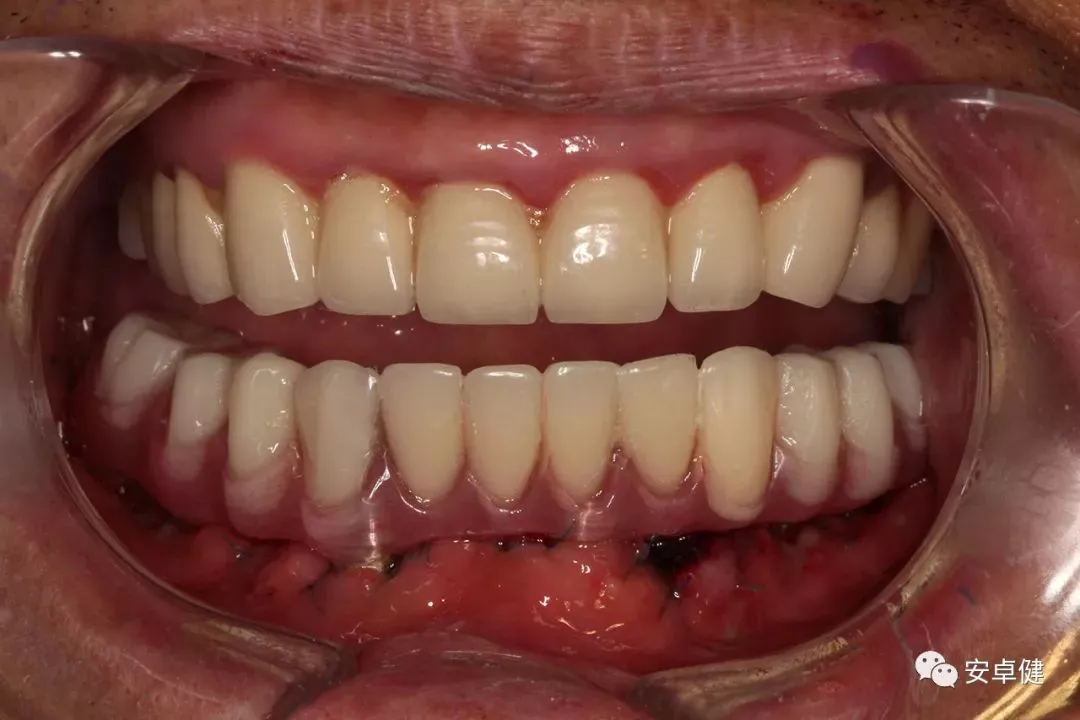

最终修复后8个月

戴牙后8个月复诊正面微张照

• 随访可见患者口腔卫生状况可,牙龈无红肿;

• 下颌修复体状态良好,无修复体机械并发症;

• 种植体基台稳定性良好,无松动;

• 种植体无松动,周围无红肿、溢脓及疼痛表现;

• 正中、前伸及侧方咬合检查可见咬合印记分布均匀,咬合关系良好;

• 患者反映日常使用良好,舒适性佳,满意度高。